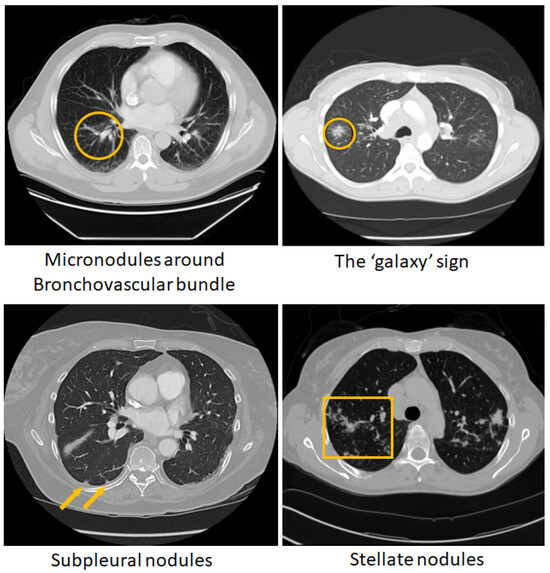

- Tana, C.; Donatiello, I.; Coppola, M.G.; Ricci, F.; Maccarone, M.T.; Ciarambino, T.; Cipollone, F.; Giamberardino, M.A. CT Findings in Pulmonary and Abdominal Sarcoidosis. Implications for Diagnosis and Classification. J. Clin. Med. 2020, 9, 3028. [Google Scholar] [CrossRef] [PubMed]

- Nakatsu, M.; Hatabu, H.; Morikawa, K.; Uematsu, H.; Ohno, Y.; Nishimura, K.; Nagai, S.; Izumi, T.; Konishi, J.; Itoh, H. Large coalescent parenchymal nodules in pulmonary sarcoidosis: “sarcoid galaxy” sign. AJR Am. J. Roentgenol. 2002, 178, 1389–1393. [Google Scholar] [CrossRef] [PubMed]

- Koide, T.; Saraya, T.; Tsukahara, Y.; Bonella, F.; Börner, E.; Ishida, M.; Ogawa, Y.; Hirukawa, I.; Oda, M.; Shimoda, M.; et al. Clinical significance of the “galaxy sign” in patients with pulmonary sarcoidosis in a Japanese single-center cohort. Sarcoidosis Vasc. Diffus. Lung Dis. 2016, 33, 247–252. [Google Scholar]

- Kuhlman, J.E.; Fishman, E.K.; Hamper, U.M.; Knowles, M.; Siegelman, S.S. The computed tomographic spectrum of thoracic sarcoidosis. Radio Graph. 1989, 9, 449–466. [Google Scholar] [CrossRef] [PubMed]

- Kumazoe, H.; Matsunaga, K.; Nagata, N.; Komori, M.; Wakamatsu, K.; Kajiki, A.; Nakazono, T.; Kudo, S. “Reversed halo sign” of high-resolution computed tomography in pulmonary sarcoidosis. J. Thorac. Imaging 2009, 24, 66–68. [Google Scholar] [CrossRef]